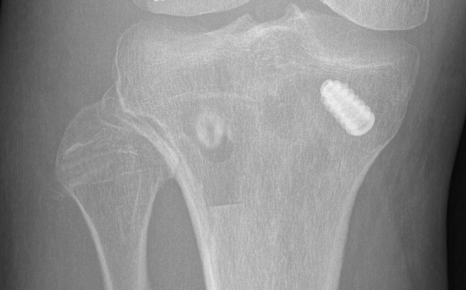

- drill 9 x 20 - 25 mm tunnel

- aim 35o anteriorly to avoid ACL tunnel

- secure 8 x 20 mm bone block with 7 x 20 mm metal screw

- aim 35o to avoid ACL tunnel

Fibular tunnel for LCL

- insertion of LCL is 8 mm from anterior fibular and 25 mm distal to fibula styloid

- tunnel will pass anterolateral in proximal fibular to posteromedial

- drill 7 tunnel protecting the CPN